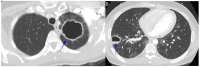

Coccidioidomycosis is a disease caused by soil fungi of the genus Coccidioides, divided genetically into Coccidioides immitis (California isolates) and Coccidioides posadasii (isolates outside California). Coccidioidomycosis is transmitted through the inhalation of fungal spores, arthroconidia, which can cause disease in susceptible mammalian hosts, including humans. Coccidioidomycosis is endemic to the western part of the United States of America, including the central valley of California, Arizona, New Mexico, and parts of western Texas. Cases have been reported in other regions in different states, and endemic pockets are present in these states. The incidence of reported cases of coccidioidomycosis has notably increased since it became reportable in 1995. Clinically, the infection ranges from asymptomatic to fatal disease due to pneumonia or disseminated states. The recognition of coccidioidomycosis can be challenging, as it frequently mimics bacterial community-acquired pneumonia. The diagnosis of coccidioidomycosis is frequently dependent on serologic testing, the results of which can take several days or longer to obtain. Coccidioidomycosis continues to present challenges for clinicians, and suspected cases can be easily missed. The challenges of coccidioidomycosis disease, from presentation to diagnosis to treatment, remain a hurdle for clinicians, and further research is needed to address these challenges.

Keywords: coccidioidomycosis; lung mass; pulmonary nodules; pyopneumothorax; valley fever.